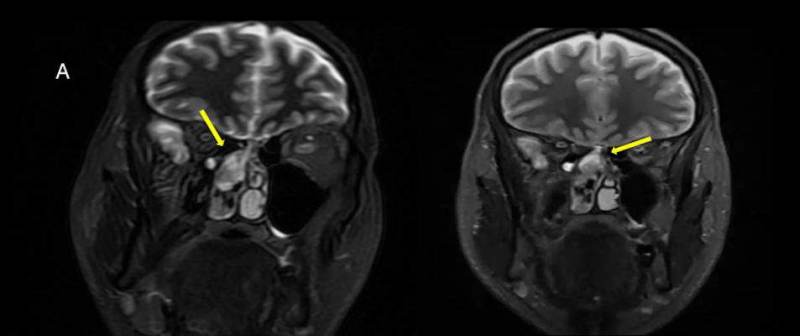

- A) Koronal T2A görntüde sağ süperior nazal kavite içerisinde hafif ekpansil karakterde, keskin sınırlı, nisbeten lobüle konturlu heterojen ara sinyal intensitye sahip yumşak doku lezyonu izleniyor (oklar).

- B) Aksiyel T2A (oklar) ve T1A (oklar) görüntülerde lezyonun süperior nazal kavitede ve ara sinyal intensitede olduğu izleniyor.